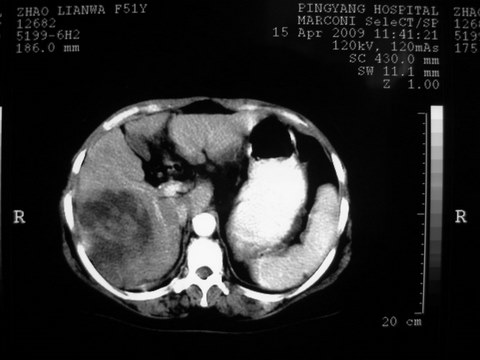

患者 女 51岁 两天前感觉上腹疼,无明显诱因,b超示肝右叶囊实性占位,边缘清楚,其内回声不均匀,ct增强如图,大家看看是什么 ,病人一年前及两月前b超检查只是提示胆囊炎

外院术后,证实肝癌合并出血

特点:1,病灶发展迅速,(2月前正常)[br] 2,囊实性,且并边界清晰光滑,呈右后叶赘生性。囊性区无强化,实性部分较多轻度强化,边界欠清。考虑囊腺癌或囊腺瘤。

出病理 中分化肝细胞癌合并出血